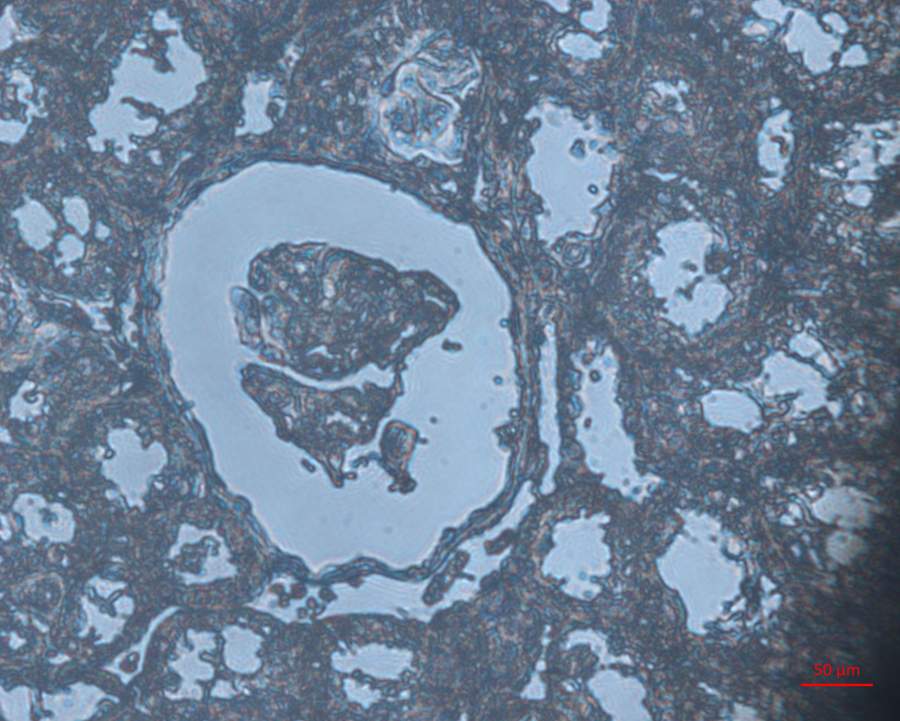

²»ºÃÒâ˼£¬ÅÄÕÕµÄʱºòÎó¼ÓÂË¹âÆ¬£¬´ó¼Ò´ÕºÏ¿´°ÉÏÈ¡£ DABȾɫ3min£¬ËÕÄ¾ËØÈ¾ÁË25s£¬ÆäËû²½Öè¶¼°´Õչ淶²Ù×÷£¬Î´¼ÓÊ÷Ö¬·âƬ¡£ Õâ¸ö½á¹û¾ÍÊÇDABȾɫ̫ÉîÁËÂ𣿠ȾµÃÊÇÉöÔà³Á×ŵÄIgG¡£ 40-1.jpg 40-2.jpg 40-3.jpg |